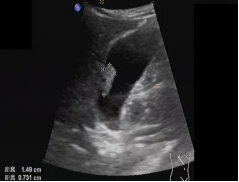

首选检查为超声检查,该检查无创、方便易行、廉价,对息肉的形态、血流有很好的判断,尤其对胆囊胆固醇沉积症、胆囊腺肌症等有独特的影像显示,是常规体检、随访的必备检查。

如超声检查探及血流信号,则肿瘤性息肉可能性大,不论息肉大小,应及时行胆囊切除术。